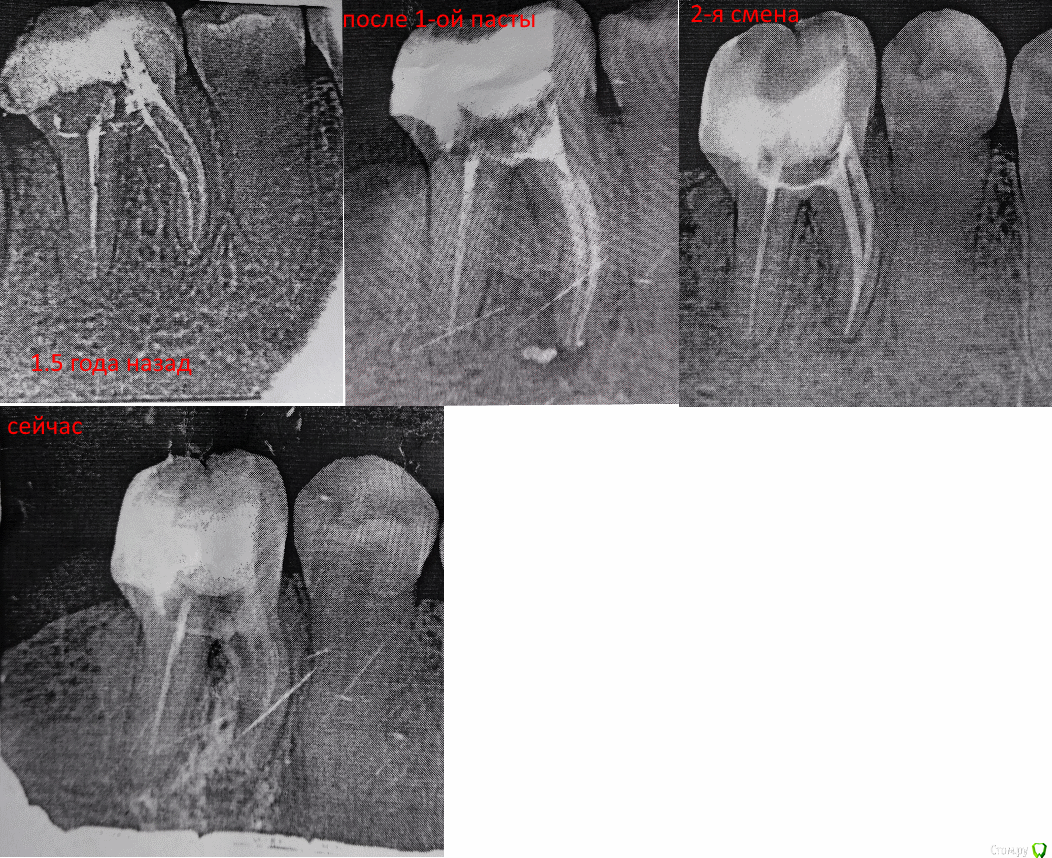

rutcode Опубликовано 10 апреля, 2017 Поделиться Опубликовано 10 апреля, 2017 Примерно полтора года назад запламбировал каналы 46 зуба при остром пульпите, после этого через год заболел зуб, возникло воспаление и образовался свищ на десне.Сделали КТ, обнаружили гранулему прим. 2.5 мм в диаметре, распломбировали каналы, положили метапекс. Отделяемое из свища исчезло в этот же день, сам свищ дня через 2-3.Воспаление также прошло.Далее под контролем рентгена 2 раза еще ложили метапекс(зуб все это время не болел), и гранулема планомерно уменьшалась, пока не исчезла вовсе. В этот момент перед окончательным пломбированием положили вместо метапекса метапасту, и я снова получил воспаление, теперь зуб терпимо болит уже 6 день, и сам ноет, и при еде.Бывает ли такая реакция на метапасту? Или это никак не связано?Врач отказывается делать снимок и говорит что все нормально, так и должно быть, бывает такая реакция на метапасту, но я не понимаю почему на метапекс ее никогда не было.PS Если бы знал, на метапасту никогда бы не согласился.PPS В период манипуляций я болел простудным заболеванием, могла ли инфекция как то попасть в зуб?PPPS Убъет ли метапаста инфекцию если она есть? Ссылка на комментарий

rutcode Опубликовано 14 апреля, 2017 Автор Поделиться Опубликовано 14 апреля, 2017 Снимки, между последними неделя. Ссылка на комментарий